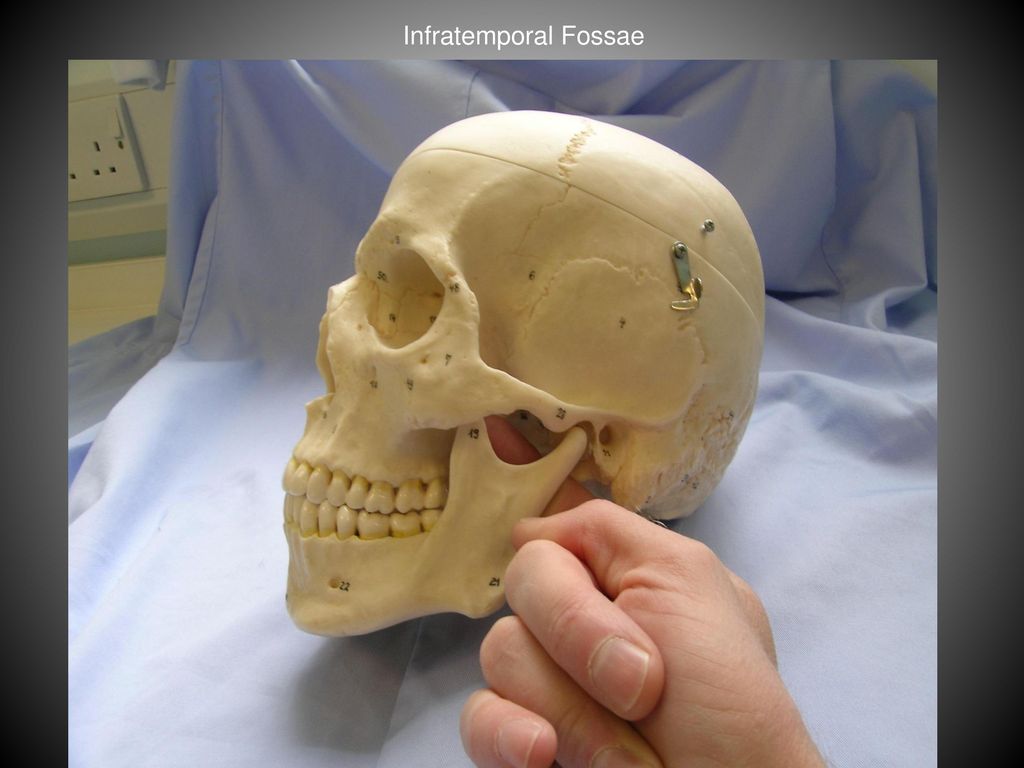

Анатомические особенности: фотографии ямок черепа, височной и подвисочной крылонебной